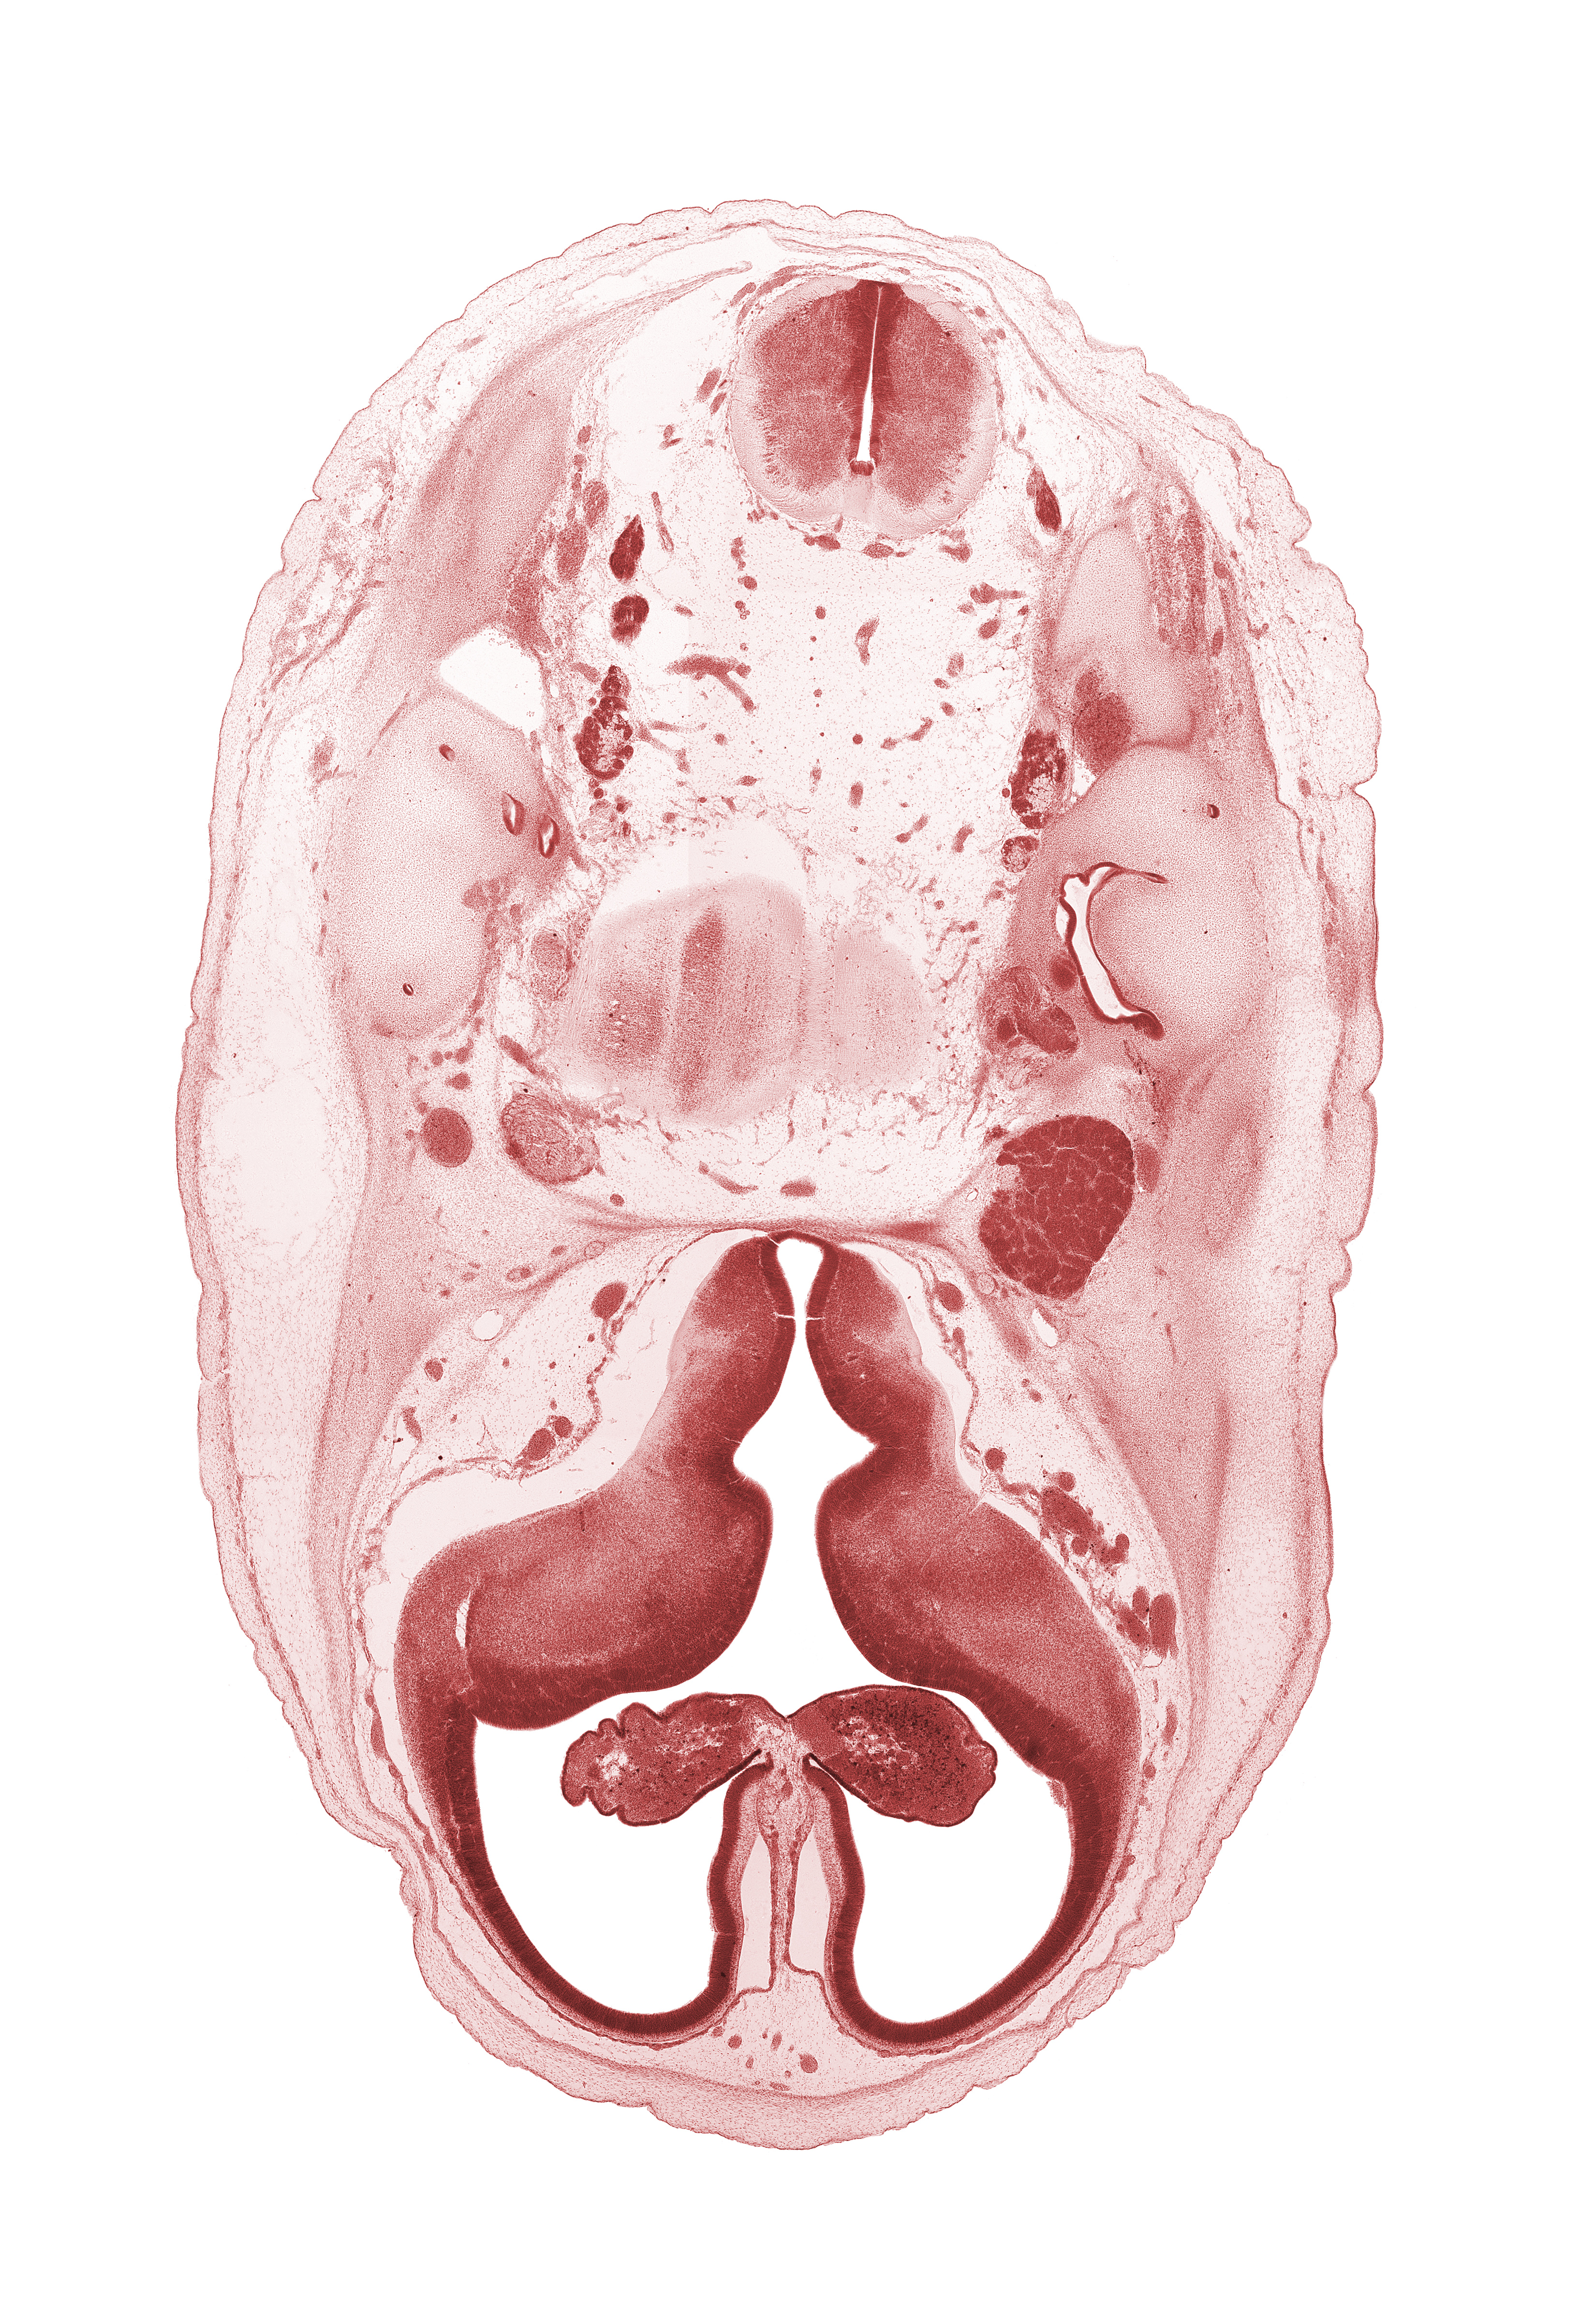

Carnegie Embryo #462 | Location: 6-01-01

Keywords: accessory nerve (CN XI), anterior semicircular duct, artifact separation(s), basilar artery, choroid fissure, choroid plexus, facial nerve (CN VII), glossopharyngeal nerve (CN IX), hypothalamic sulcus, internal carotid artery, lateral ventricular eminence (telencephalon), medial ventricular eminence (diencephalon), myelencephalon (medulla oblongata), pons region (metencephalon), posterior semicircular duct, root of abducens nerve (CN VI), root of hypoglossal nerve (CN XII), trigeminal ganglion (CN V), vagus nerve (CN X), vestibulocochlear ganglion (CN VIII)

Source: The Virtual Human Embryo.